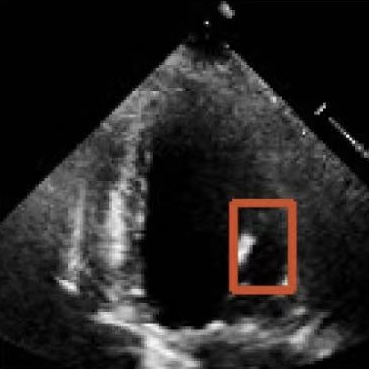

Figure 1: Illustrative challenges for echocardiography video segmentation: (a) speckle noise, (b) indistinct or blurred contours, and (c-f) the substantial changes in the target’s shape and scale throughout the cardiac cycle.

However, achieving precise segmentation in echocardiography faces severe challenges stemming from poor image quality and complex cardiac dynamics. Figures 1(a) and 1(b) show that ultrasound images are characterized by high speckle noise and low contrast, which obscure tissue structures and lead to weak or incomplete anatomical boundaries. These artifacts hinder the model’s ability to learn robust features and can result in the inaccurate segmentation. In the temporal dimension, the heart undergoes significant non-rigid deformation throughout the cardiac cycle. Figures 1(c), 1(d), 1(e) and 1(f) show that, the shape and scale of the LV change dramatically between systole and diastole. This substantial dynamic variation demands that segmentation models possess strong temporal modeling capabilities to accurately track the changing appearance of the target across the video sequence [20].